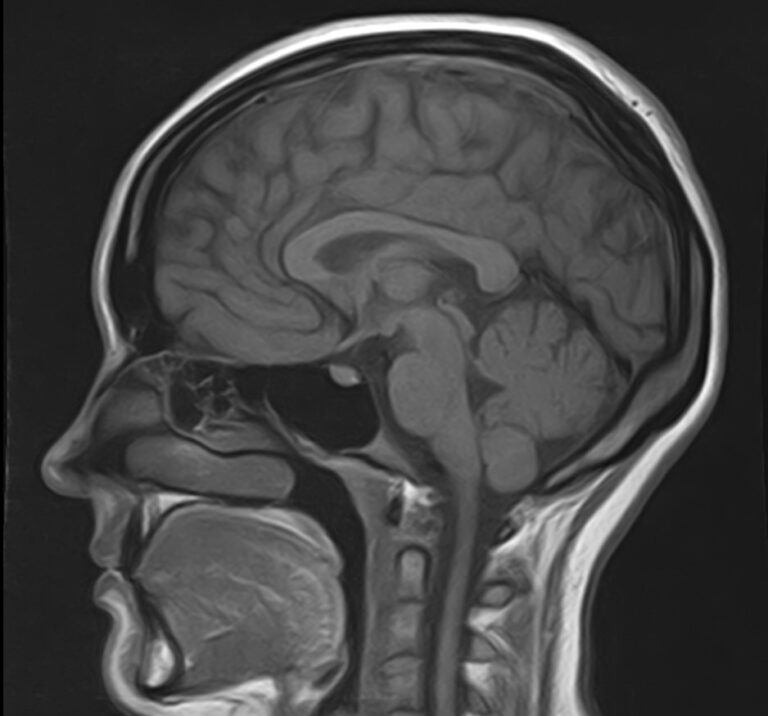

Сканирование проводится на современном высокопольном магнитно-резонансном томографе закрытого типа TOSHIBA VANTAGE TITAN 1,5 Тесла, который делает послойные срезы в разных плоскостях с шагом от 1 мм и на основе полученных данных создает трехмерные изображения превосходного качества. Метод исследования позволяет в мельчайших подробностях визуализировать состояние всех структур головного мозга и шейного отдела позвоночника, что дает возможность выявлять патологические изменения на ранних стадиях и назначать своевременное лечение.